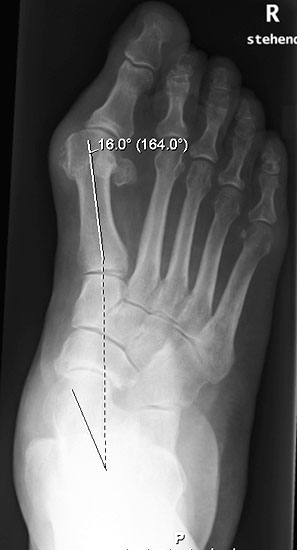

Der Talo-Metatarsale I Winkel bzw. die laterale talonaviculare Subluxation auf der stehenden dorsoplantaren Aufnahme des Fuβes dokumentieren das Ausmaβ des Vorfuβ abductus (Abb. 6 a,b). Ein dp Talo-Metatarsale I Winkel von > 10° (nach medial konvex) ist als pathologisch anzusehen. Mit der Bestimmung der talocalcanearen Divergenz (Abb. 6 c) erhält man ein Eindruck über das Ausmaβ des Rückfuβ valgus; eine leichte Divergenz bis ca. 12° gilt als physiologisch 20.